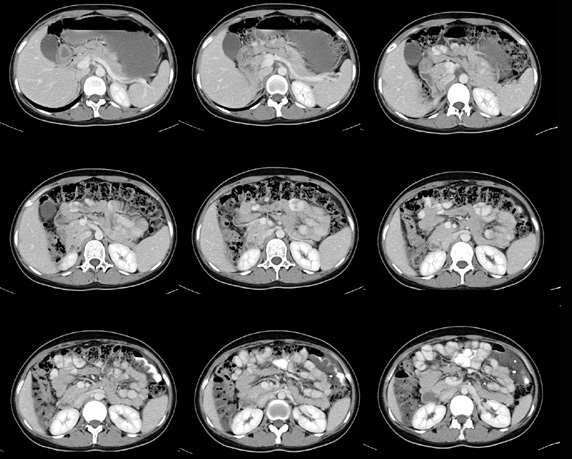

女性,28岁,停经3月,腹部膨隆1月,产前检查发现腹部占位

{肿块中心ct值27hu,增强后,动脉期、门脉期均无明显强化)

1 肠系膜肿块诸期无明显强化,肠系膜血管包绕其中但其周围仍见脂肪称“脂肪环征”;2 肠系膜血管远端较近端细,于重组像上见血管周围有强化结节为炎性结节,3肿块内见部分脂肪密度及少许点状钙化。4 腹膜后无肿大ln。

患者手术病理:腹腔囊性淋巴管瘤,象这样充满整个腹腔的的确很少见